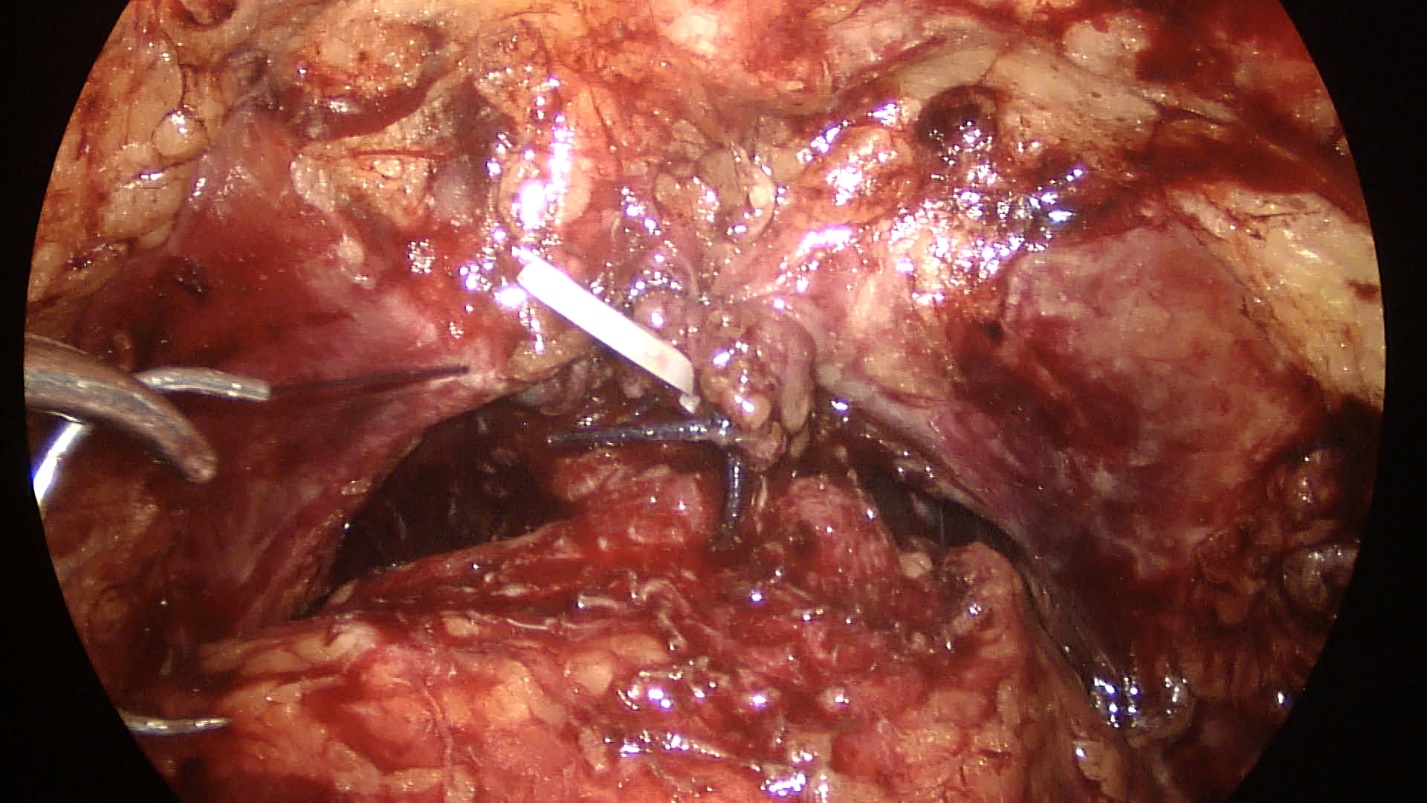

The third patient underwent endovideosurgical RPE with preservation of both NVBs also using Hem-o-Lok clips. The postoperative period was uneventful; the patient holds urine from the first day of catheter removal. There was a gradual deterioration of urination, thinning of the urine stream and occasional impurity of blood in the urine after 4 years and 2 months after surgery. The patient was taking alpha-adrenoblockers and phytopreparations with no significant positive effect. During examination, CT scan of the pelvis revealed an irregularly shaped bladder concrement fixed to its posterior wall with the dimensions of 3×4 cm (Fig. 4). The patient underwent urethrocystoscopy with laser cystolithotripsy. Six Hem-o-Lok clips were detected after stone fragmentation, immersed in the thickness of the posterior wall of the urinary bladder cervix at different depths (Fig. 5). There was performed photovaporization of scar tissues around the clips with their subsequent removal with forceps. The postoperative period proceeded without complications, the urethral catheter was removed on the fourth day. The complaints of dysuria and hematuria are resolved; the patient holds urine completely.

Fig. 5. Removed Hem-o-Lok clips and fragmented concrement